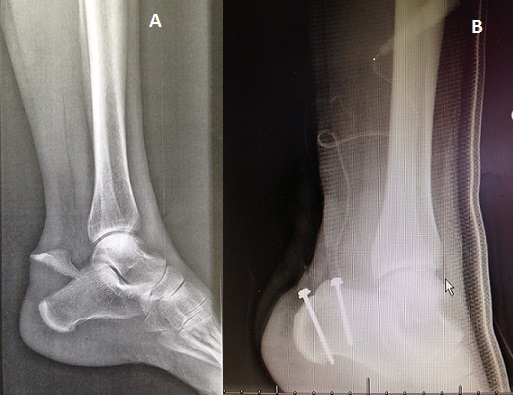

Les fractures de calcaneum constituent 60% des fractures de tarse et 02% de l'ensemle des fractures.La fracture en bec de canard de la tuberosité posterieure, appelée également avulsion de l'insertion du tendon d'achile est une entitée encore plus rare mais de bon pronostic. Dans notre cas, on decrit l'observation d'un jeune homme de 24 ans , sans antecedents pathologiques notables, qui a présenté suite a un accident de sport survenu lors d'un match de foot , après une sensation de craquement au niveau de l'arrière pied gauche, une cheville gauche oedematiée,ecchymotique,avec impotence foctionnelletotale,impossibilité de se tenir debout sur la pointe du pied gauche et un signe de Thompson positif a gauche.Un bilan radiologique fait d'une radiographie standard de la cheville a objective une fracture extra-thalamique du calcaneum interessant la tuberosité posterieure, en bec de canard. La prise en charge a consisté en une intervention chirurgicale sous rachi-anesthesie pendant laquelle on a realisé un vissage direct,completé par une botte platrée en équin pendant 04 semaines , avec interdiction de l'appui, sous couvert d'une anticoagulation a dose prophylactique, suivie après l'ablation du plâtred'une reeducation fonctionnelle. Le résultat avec un recul de 01 an était satisfaisant avec une bonne évolution clinique et radiologique. Les fractures en bec de canard du calcaneum sont rares mais de bon pronostic.